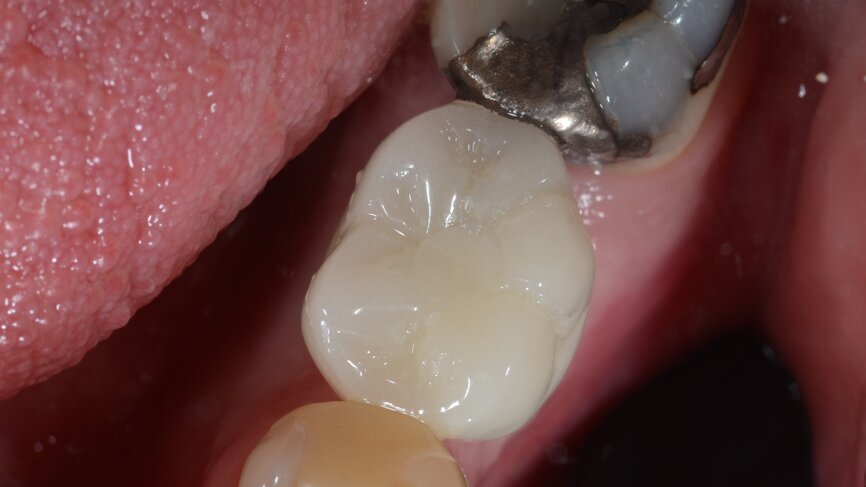

Fig. 17: Final crown in position, occlusal view.

Fig. 20: One-year follow-up occlusal view.